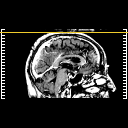

Glioma overlay -- Slice #120

[Home][Help][Clinical] Slice 120